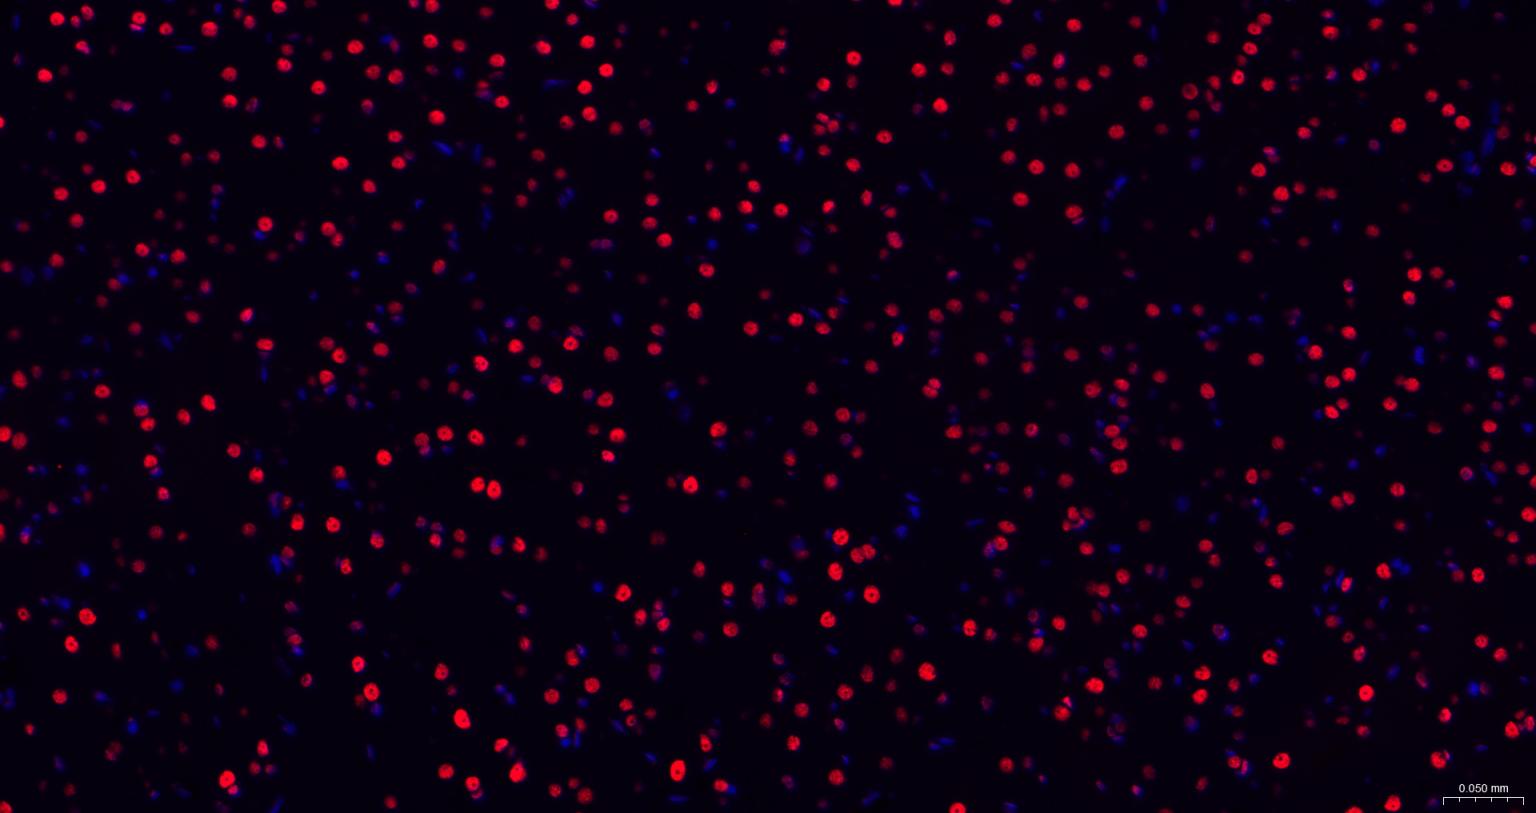

Paraformaldehyde-fixed, paraffin embedded Human Cerebrum; Antigen retrieval by boiling in sodium citrate buffer (pH6.0) for 15 min; The section was incubated with TARDBP Monoclonal Antibody, Unconjugated (bsm-52949R) at 1:200 overnight at 4°C. Followed by conjugated Goat Anti-Rabbit IgG antibody (Red, bs-0295G-BF594), DAPI (blue, C02-04002) was used to stain the cell nuclei.